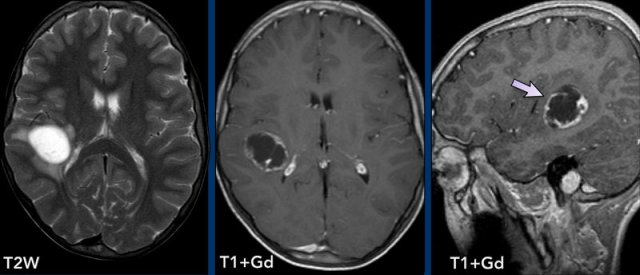

Pyogenic Abscess

The various MR-findings of a pyogenic abscess are shown in the table.

The most typical finding is a peripherally-enhancing lesion with central diffusion restriction.

These images are of a 55-year old male with headache.

First look at the images and then continue reading.

Question:

- What is the most likely diagnosis?

- Which findings

are typical for this diagnosis?

The findings are:

- There are two ring enhancing lesions surrounded by edema

- On the T2W-image a double rim sign is present in the left frontal lesion.

- There is central diffusion restriction.

- There is smooth enhancement.

All these findings are

consistent with the diagnosis of cerebral abscesses.

A double rim on T2W-images can be seen in up to 75% of cases.

Classically there is a complete rim

enhancement and diffusion restriction, but sometimes there is incomplete enhancement as the abscess points

towards the ventricle, ready to empty the pus into the ventricular system.

You

can see the beginning of that process in the right frontal abscess.

When this abscess ruptures into the ventricle the rim will be interrupted and there will be

diffusion restriction within the ventricle.